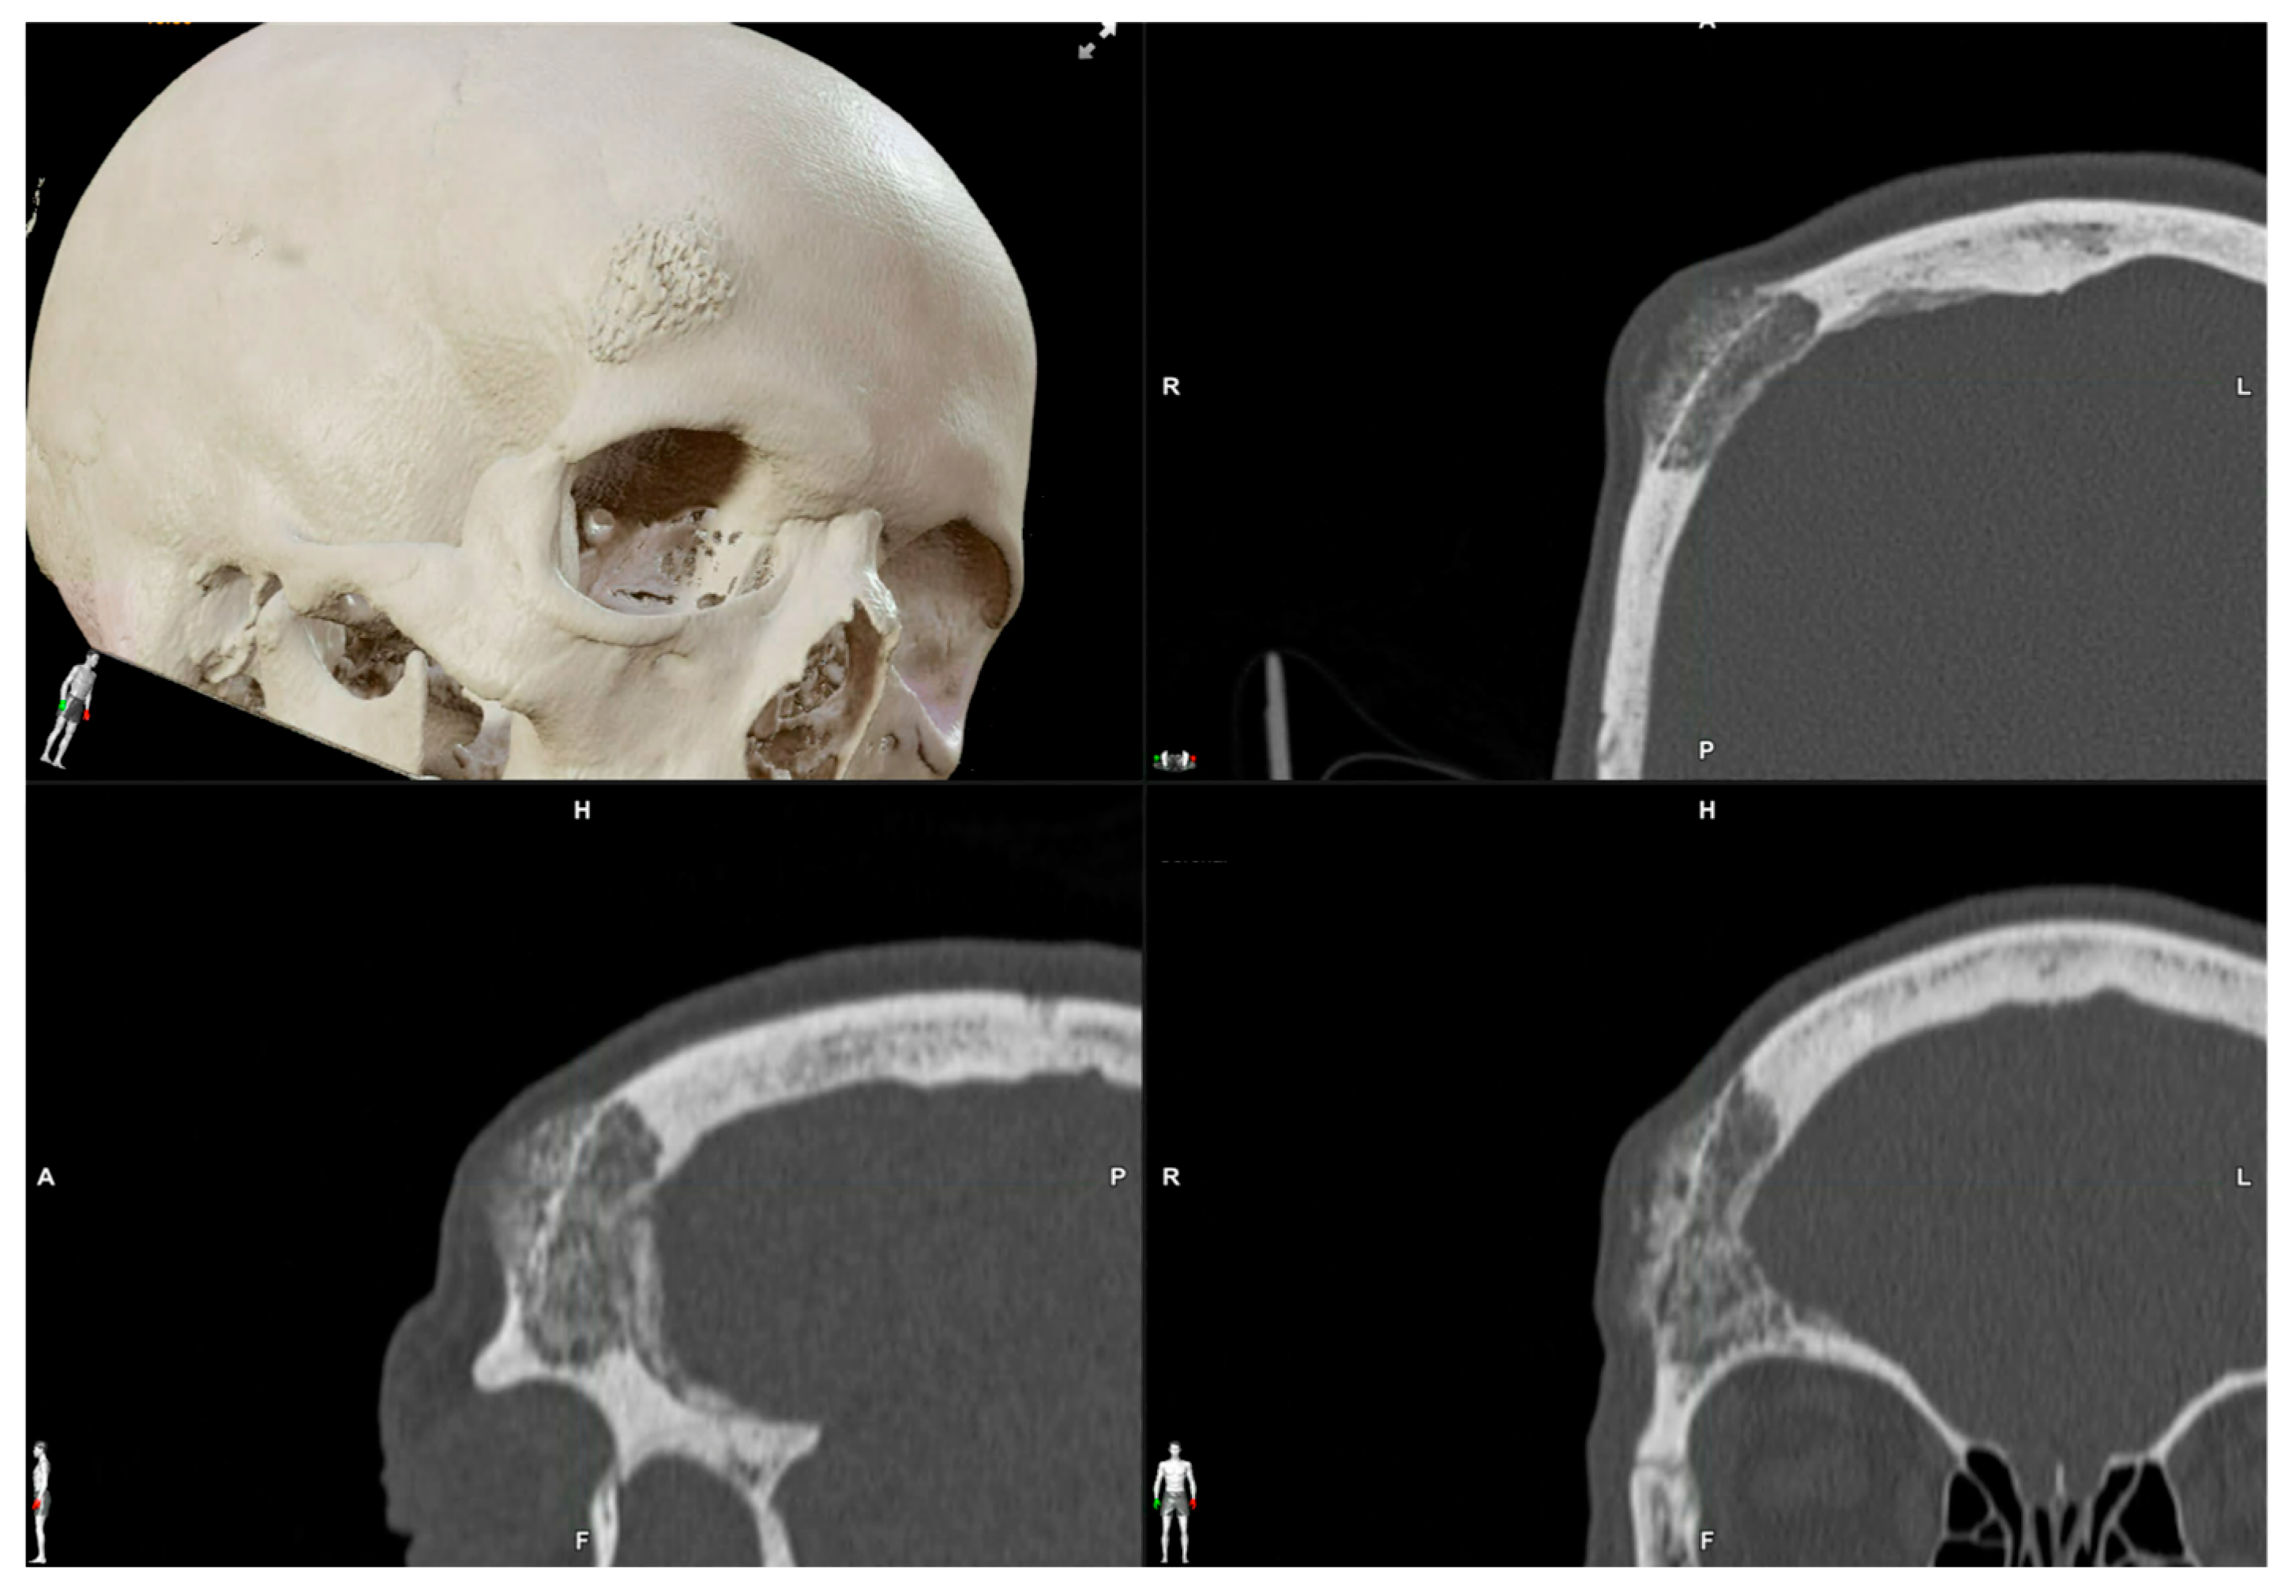

2.3.1. Virtual Surgical Plan

| 1 | 53/F | L/25 mm | Y | 4 mo | Dystopia | N | CT, MRI | Supraorbital rim, orbital roof | Intraosseous venous malformation | - | Resection + reconstruction | Y | Y | 1st, 2nd, 3rd | Coronal | Y | Piezoelectric device | N | PEEK prosthesis | 7 y/N |

| 2 | 54/F | R/33 mm | Y | 9 y | N | Y | CT, MRI | Frontal bone, orbital roof | Intraosseous venous malformation | - | Resection + reconstruction | Y | Y | 1st, 2nd, 3rd | Coronal | Y | Piezoelectric device | N | PEEK prosthesis | 6 y/N |